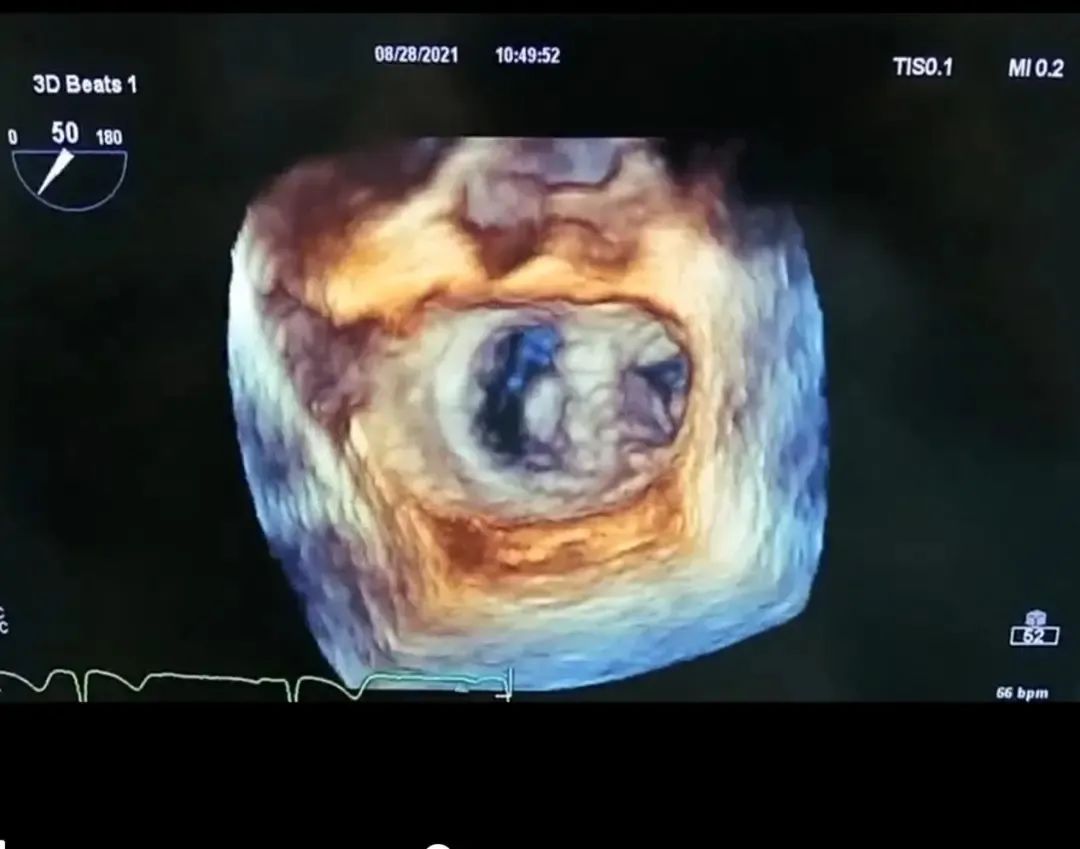

心脏彩超检查均提示:二尖瓣前叶(A2)或者后叶(P2)脱垂,部分病例存在腱索断裂,二尖瓣关闭不全,重度反流。

术前超声心动图

术后超声心动图

术后二尖瓣口血流

术后肺静脉血流